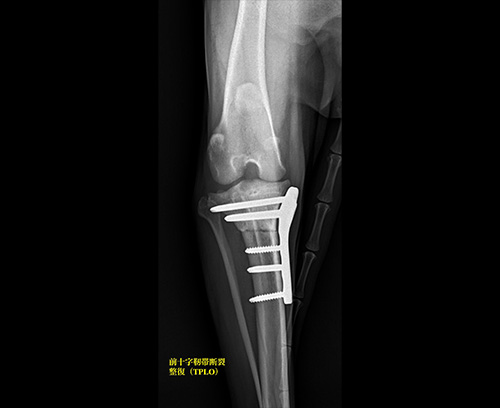

前十字靭帯断裂(TPLO)

十字靭帯断裂(TPLO)